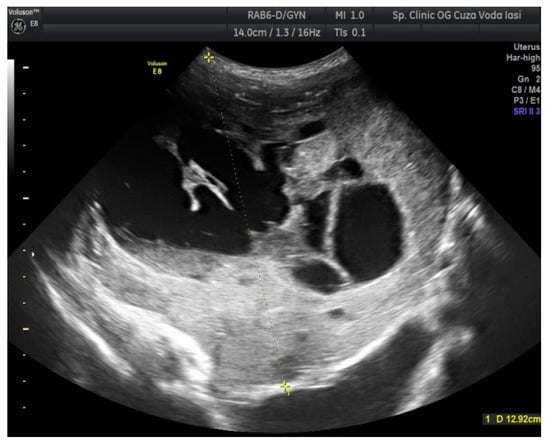

2. Case Presentation